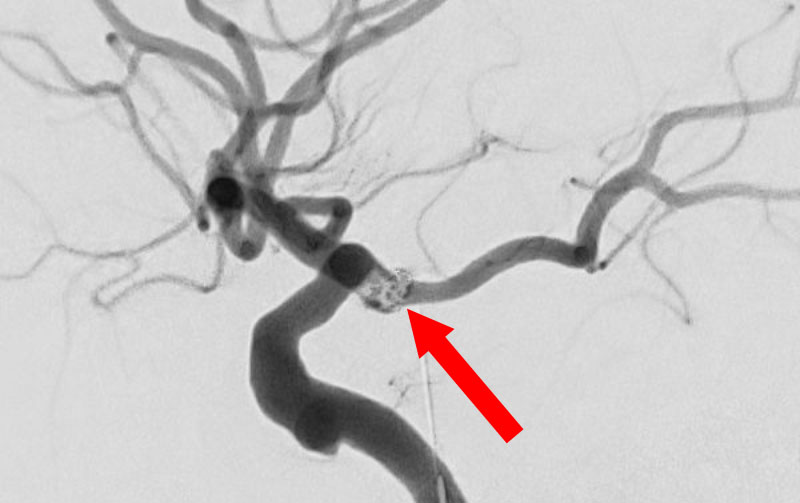

No.1631 手術中